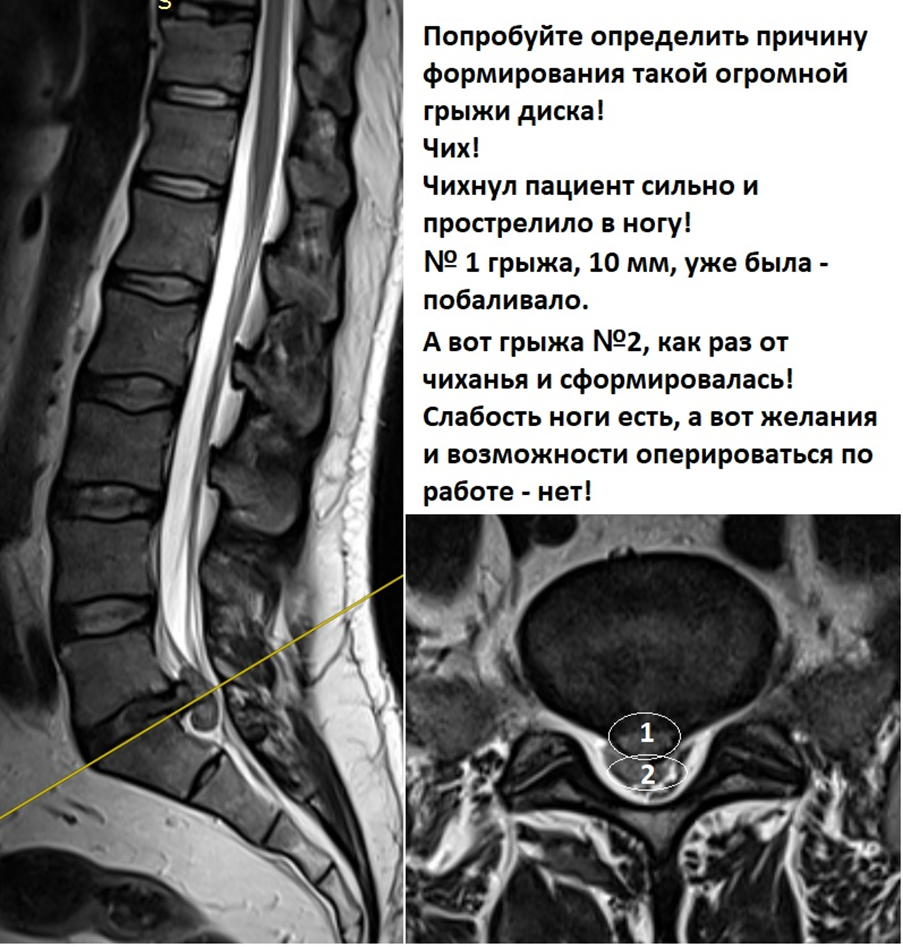

ПОПРОБУЙТЕ ОПРЕДЕЛИТЬ ПРИЧИНУ ТАКОЙ ОГРОМНОЙ ГРЫЖИ ДИСКА!

Чихнул пациент сильно и прострелило в ногу.

Грыжа №1 10 мм уже была, а при движении позвоночника в момент чиха в пораженном сегменте, так как мышцы в этот момент расслаблены, произошло дополнительное выдавливание.

Надо учитывать, что во всем этом процессе участвуют и эпидуральные вены.

Огромная грыжа межпозвонковго диска возникшая в момент чихания.